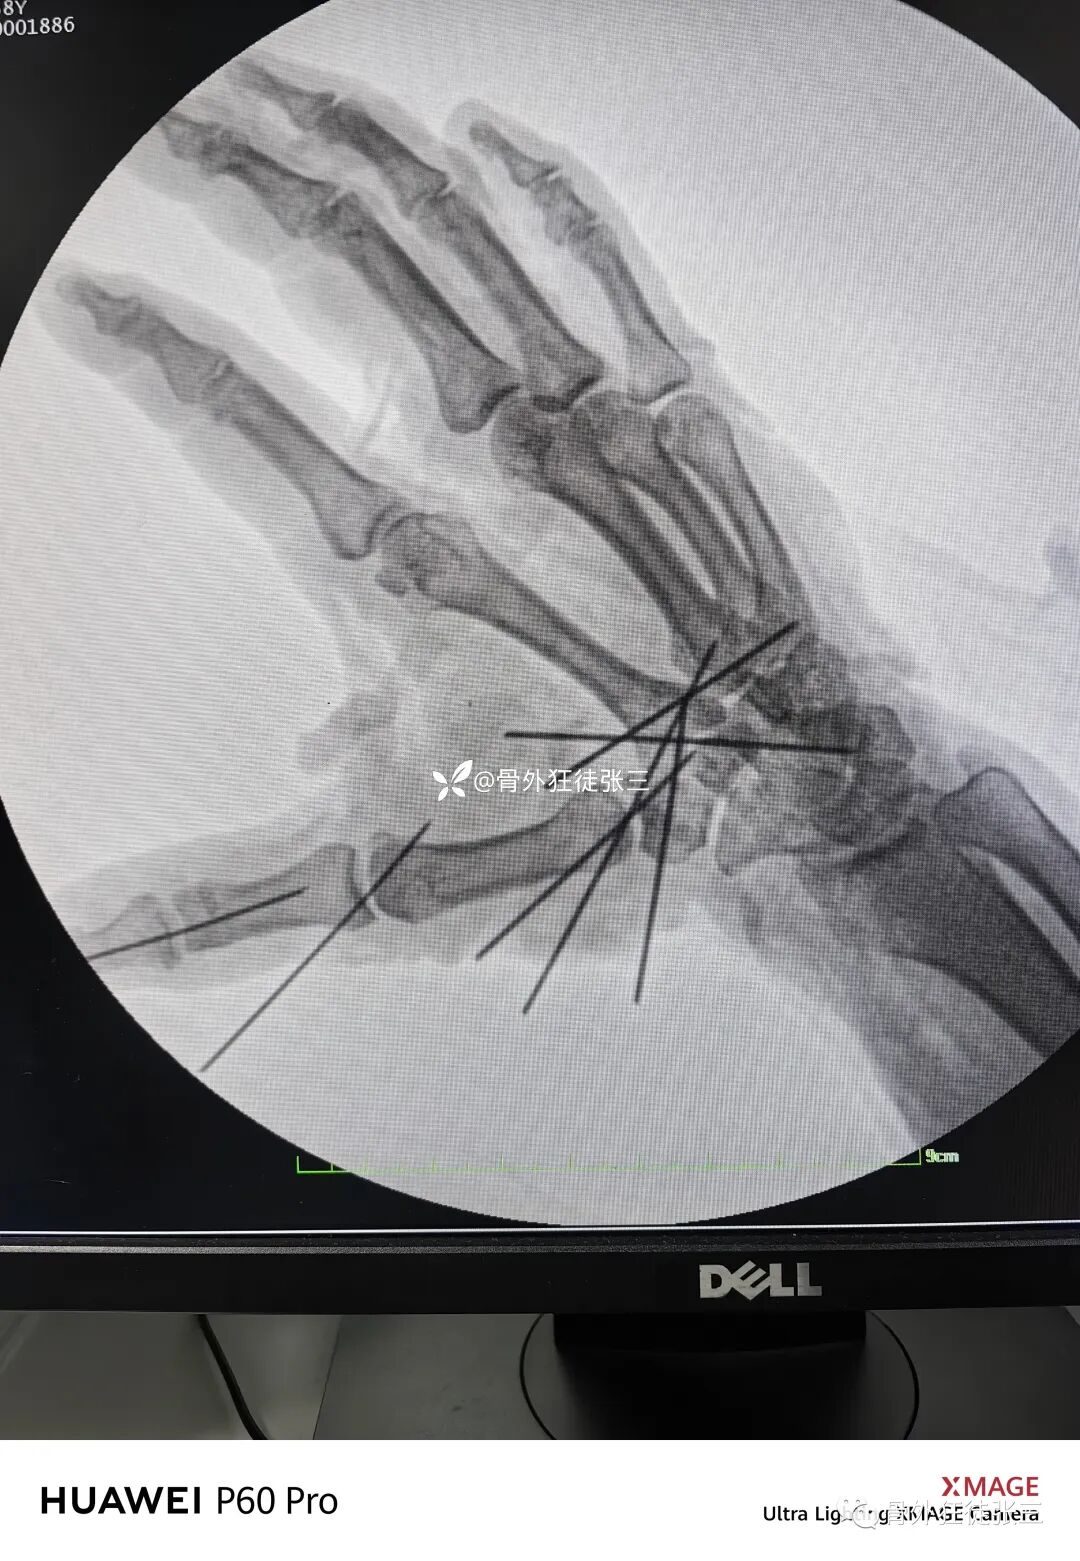

病例8,第234跖骨骨折,闭合穿针

病例32,第345掌骨开放性骨折,克氏针髓内+克氏针支架

病例33,开放性Lisfranc损伤+第2345跖骨骨折脱位

病例42,人工股骨头置换术后感染,spacer置入

病例48,多发跖骨骨折脱位,克氏针